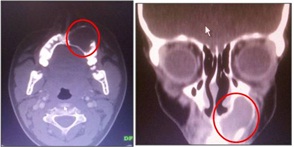

OPG confirmed our diagnosis and supplemented by showing deviation of 23,24 in order to accommodate the radiolucent mass which was a typical finding in present case [Table/Fig-5]. On performing Fine Needle Aspiration Cytology (FNAC) it showed straw coloured fluid was collected and cytology confirmed presence of paucicellular cells like polymorphs, macrophages and few squamous epithelial cells. CT scan in axial and coronal view suggested radiolucent growth in relation to left side of maxilla involving 21,22,23,24 [Table/Fig-6].

CT scan in an axial and coronal section showing radiolucent lesion on apical area of maxillary anteriors